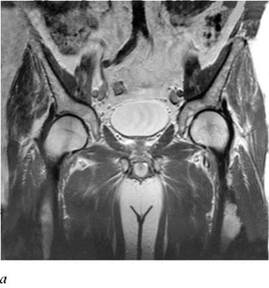

МРТ позволяет получать изображения в трех взаимно перпендикулярных проекциях - поперечной (аксиальной), фронтальной (корональной) и сагиттальной, а также в косых (наклонных) проекциях(рис. 4.38, 4.39).

Рис. 4.39. МРТ малого таза в норме: а - фронтальная проекция; б - сагиттальная проекция